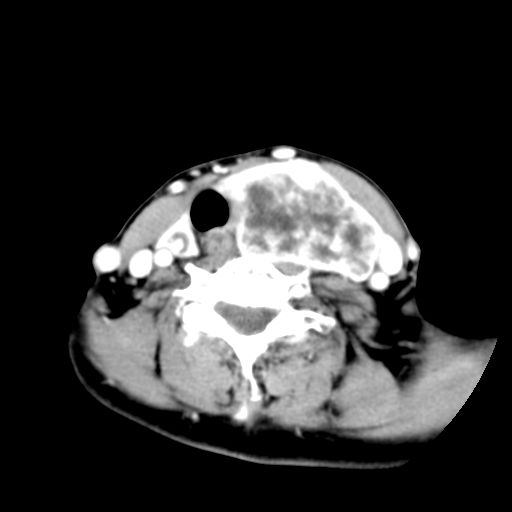

女  53岁  左侧甲状腺肿物3年,近2月明显增大。病理稍后发。

左侧甲状腺内见有一较大类圆形低密度区,边缘清楚光整,增强有一定强化,但仍较正常甲状腺组织强化弱,左侧甲状腺周围组织明显受压移位,且周围组织界限存在,周围组织间隙内未见肿大淋巴结,结合病史考虑为良性病变,左侧甲状腺腺瘤可能大。

左侧甲状腺内见有一较大类圆形低密度区,边缘清楚光整,增强有一定强化,但仍较正常甲状腺组织强化弱,左侧甲状腺周围组织明显受压移位,且周围组织界限存在,周围组织间隙内未见肿大淋巴结。

考虑:甲状腺囊腺瘤

双侧都有,最大病灶在左侧,其包膜和灶内部都有明显的强化,提示其血供丰富。我首先考虑是良性占位,以腺瘤可能性大。

左侧甲状腺内见有一类圆形低密度区,边缘清楚光整,可见明显增强,间隔亦可见增强,且与周围组织分解清晰,周围组织间隙内未见肿大淋巴结。右侧亦可见类似表现。考虑甲状腺腺瘤。

手术病理证实:双侧腺瘤样甲状腺肿。